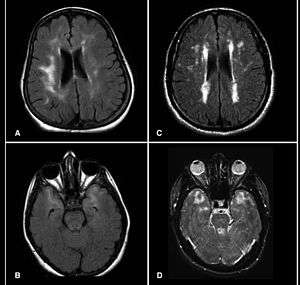

Hyperintensities refer to areas of high intensity on types of magnetic resonance imaging (MRI) scans of the human brain or that of other mammals. These small regions of high intensity are observed on T2 weighted MRI images (typically created using 3D FLAIR) within cerebral white matter (white matter lesions, white matter hyperintensities or WMH)[1] [2] or subcortical gray matter (gray matter hyperintensities or GMH). They are usually seen in normal aging but also in a number of neurological disorders and psychiatric illnesses. For example, deep white matter hyperintensites are 2.5 to 3 times more likely to occur in bipolar disorder and major depressive disorder than control subjects.[3][4] WMH volume, calculated as a potential diagnostic measure, has been shown to correlate to certain cognitive factors.[5] Hyperintensities appear as "bright signals" (bright areas) on an MRI image and the term "bright signal" is occasionally used as a synonym for a hyperintensity.

Hyperintensities are commonly divided into 3 types depending on the region of the brain where they are found. Deep white matter hyperintensites occur deep within white matter, periventricular white matter hyperintensities occur adjacent to the lateral ventricles and subcortical hyperintensities occur in the basal ganglia.